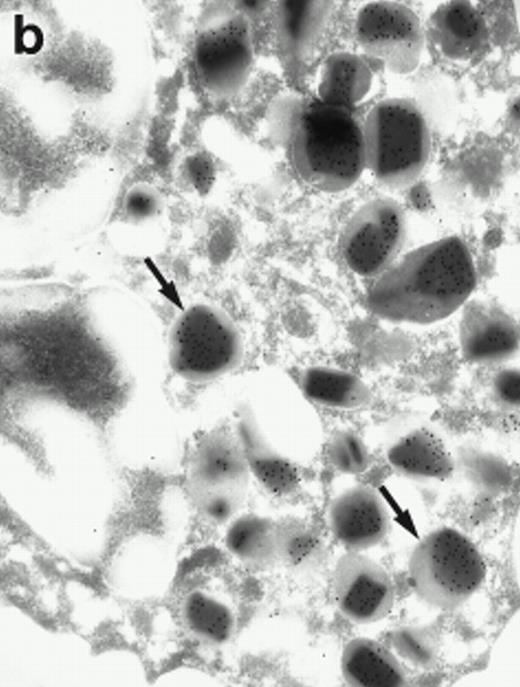

Morphologic analyses of both mature eosinophils and day-24 IL-5–induced UCC by immunoelectron microscopy were performed with proMBP-specific monoclonal antibody (J163-15E10) and with polyclonal antibody to MBP (rabbit #14). No proMBP staining was observed in peripheral blood eosinophils (Fig 6a); in contrast, MBP was localized specifically to the granule crystalline core (Fig 6b). Day-24 IL-5–induced UCC showed marked proMBP labeling of large uncondensed granules and minimal labeling of small condensed granules (Fig 6c); remarkably, proMBP was often seen as a ring around what appeared to be a granule in the process of condensing (black arrow). MBP labeling was confined primarily to condensing granules (Fig6d). Figure 7 shows results from double immunogold labeling of both proMBP (small gold) and MBP (large gold). ProMBP was concentrated in large uncondensed granules, and MBP was concentrated in condensed granules. Some granules (black arrow in Fig7b) contained labeling for MBP (primarily in the center) and proMBP (at the periphery). Controls using either normal mouse immunoglobulin or normal rabbit immunoglobulin as the primary label were negative (results not shown).

Localization of proMBP and MBP by immunoelectron microscopy. (a) A peripheral blood eosinophil labeled with anti-proMBP J163-15E10. Note the absence of specific labeling. (b) A peripheral blood eosinophil labeled with rabbit anti-MBP. Note that MBP is specifically localized to the granule crystalline core (black arrows). (c) Day-24 IL-5–induced UCC labeled with anti-proMBP. The black arrow shows localization of proMBP predominantly to the periphery of a condensing granule; very little proMBP is present in the interior of that granule. The white arrow points to a condensed granule, which lacks proMBP label. Also, note the presence of a large uncondensed granule densely labeled with proMBP proximal to the nucleus (open white arrowhead). (d) Day-24 IL-5–induced UCC labeled with anti-MBP. MBP is localized primarily to the interior of condensing granules (black arrows). (a, c, and d) Original magnification ×11,000; (b) ×15,000.

Localization of proMBP and MBP in day-24 IL-5–induced UCC by immunoelectron microscopy using double labeling. ProMBP was localized with 15-nm colloidal gold particles and MBP with 30-nm gold particles. (a) Although proMBP labeling (small gold) is seen throughout the Golgi, it is concentrated predominantly in the large uncondensed granules (white arrow); only minimal MBP labeling (large gold) is evident in the large granules. In contrast, the small condensed granules show marked MBP labeling in the interior and minimal proMBP labeling at the periphery (black arrow). (b) At higher magnification, dense labeling for proMBP (small gold) and minimal labeling for MBP (large gold) is evident in a large uncondensed granule (white arrow). The black arrow identifies a small condensed granule that contains predominantly MBP, along with minimal proMBP at the periphery. (a) Original magnification ×11,000; (b) ×20,000.